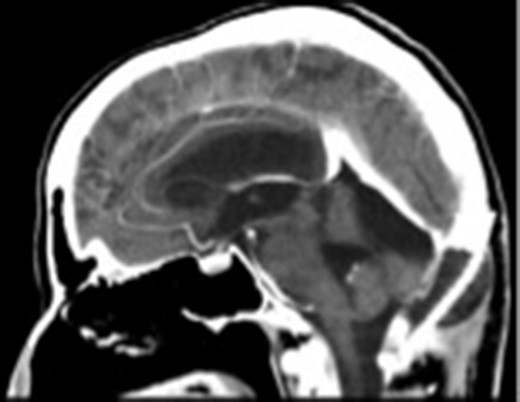

The postoperative sagittal contrast-enhanced CT scan showing that the tumor had been totally excised.